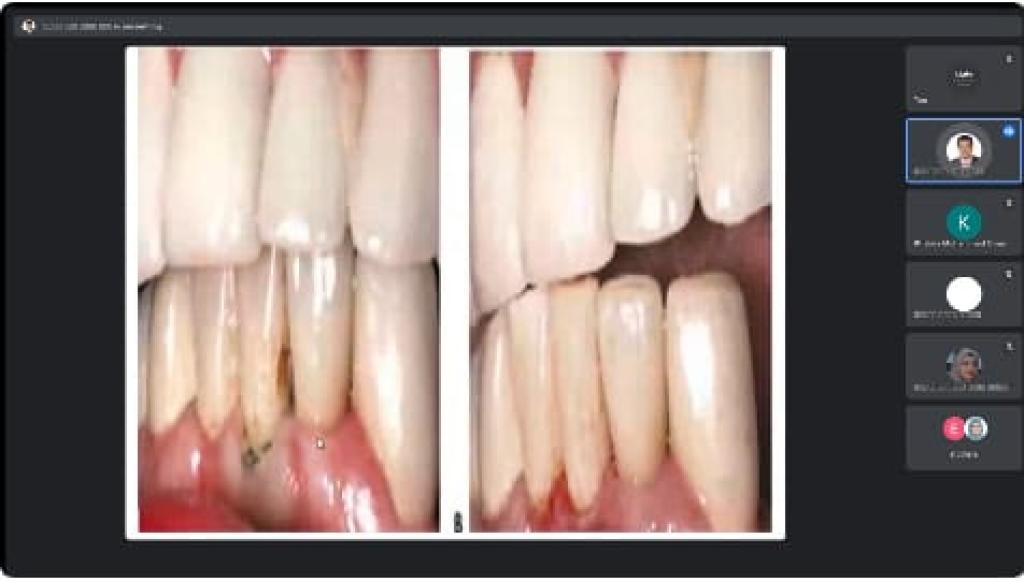

برعاية السيد رئيس جامعة الموصل الأستاذ الدكتور قصي كمال الدين الاحمدي وبإشراف السيدة عميد كلية العلوم الأستاذ الدكتورة هيام عادل إبراهيم وضمن نشاطات التعليم المستمر في كليتنا ، أقيمت في قسم الفيزياء الطبية دورة علمية عبر الفضاء الإلكتروني بعنوان ” الاسمنت الطبي في مفهوم الفيزياء الطبية ” للفترة 3 – 5 كانون الثاني 2023 .تضمنت محاضرات اليوم الأول التي القاها أ.م.د. قصي خطاب عمر الاسمنت الطبي كعلاج فقرات العمود الفقري ، الاسمنت الطبي يستخدم في جراحة المفاصل و هشاشة العظام ، الاسمنت العظمي العلاج الأمثل لآلام المفاصل بدون جراحة فضلاً عن الاسمنت العظمي مكوناته وخواصه الفيزيائية .بينما تطرّق في اليوم الثاني عن تشخيص الاسمنت الطبي بكل أنواعه باستخدام عدة تقنيات منها ( باستخدام الأشعة السينية التقليدية ، باستخدام جهاز CT scan ، باستخدام الرنين المغناطيسي ، باستخدام جهاز PET المسح البوزتروني ) .وفي اليوم الثالث والأخير القى م.د. محمود أحمد محمد فخري محاضرة عن بعض خواص الاسمنت الطبي وطرق تحضيره سريراً ، ومدى تأثر التركيب النهائي له بطرق التحضير الآنية ، وماهي فائدة بعض الاضافات لتركيبة الاسمنت الطبي ، كما تضمنت المحاضرة حقنة الاسمنت الطبي لمعالج كسور الفقرات الناتجة عن هشاشة العظام بالدرجة الأولى أو بعض الحوادث أو الأمراض الأخرى المؤدية إلى ضعف الفقرات وظهور هذه الكسور.شعبة الإعلام والعلاقات العامةالجمعة 6 كانون الثاني 2023